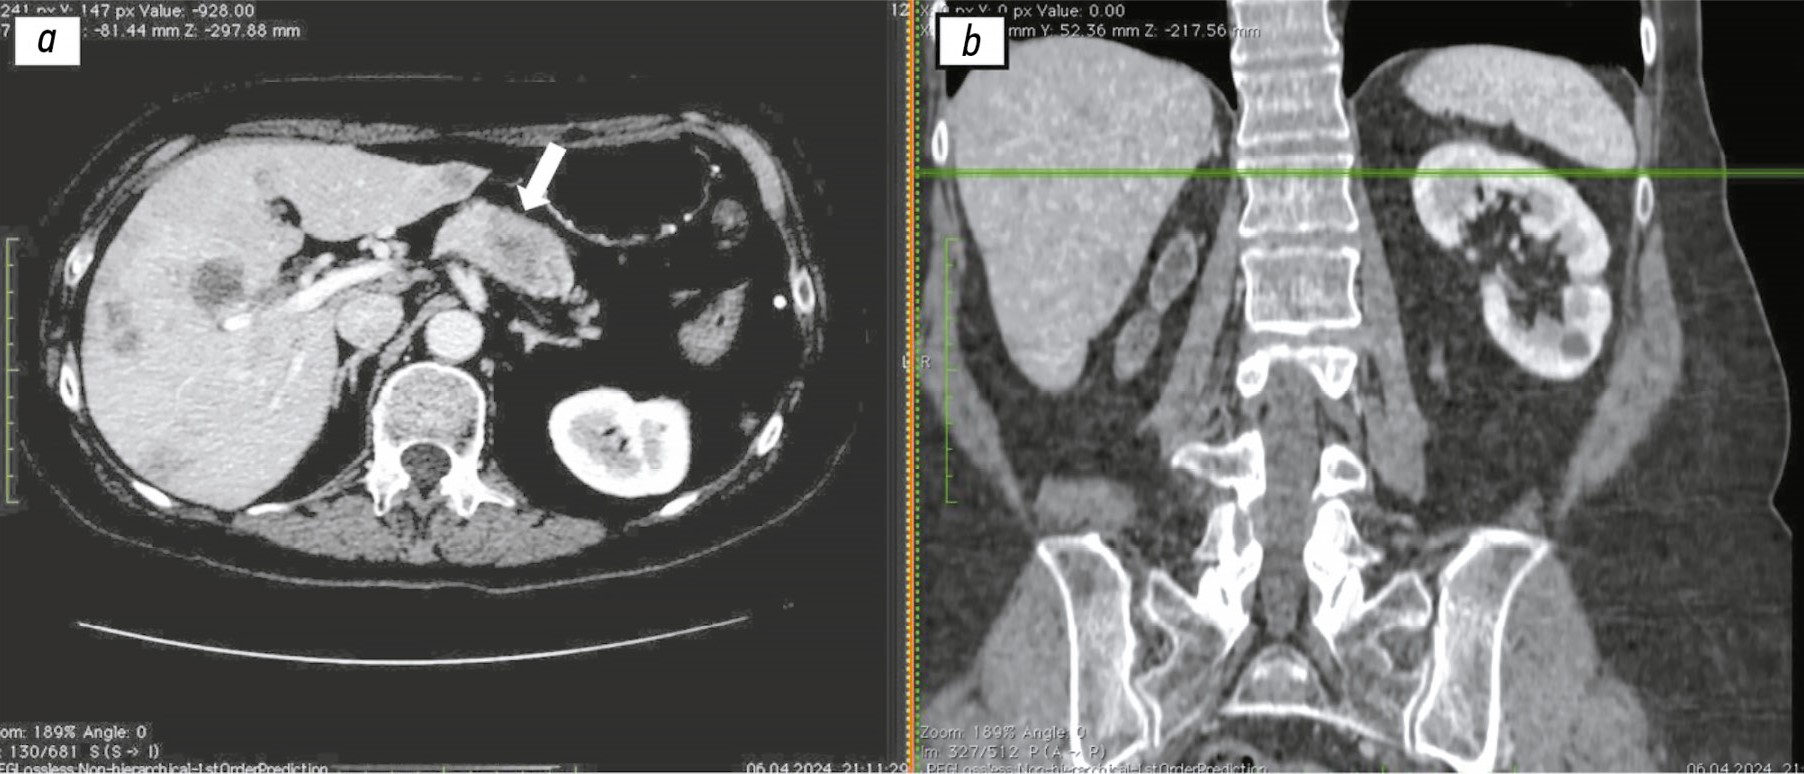

Nonbacterial thrombotic endocarditis of the tricuspid valve with recurrent pulmonary embolism in a patient with pancreatic adenocarcinoma: a case report

Nonbacterial thrombotic endocarditis is a rare condition that is typically asymptomatic and is most often diagnosed post mortem in patients with cancer, systemic lupus erythematosus, or antiphospholipid syndrome. In this condition, vegetations are predominantly localized in the left heart. In contrast, isolated involvement of the tricuspid valve in nonbacterial thrombotic endocarditis is extremely rare, and the the incidence of this localization has not been established.

This article presents a clinical case of nonbacterial thrombotic endocarditis in a patient with pancreatic cancer and liver metastases, characterized by a rare variant of isolated tricuspid valve involvement and manifested by recurrent episodes of pulmonary embolism despite ongoing anticoagulant therapy.

The complexity of this case was due to recurrent pulmonary embolism following any attempt of even short-term discontinuation of anticoagulant therapy. At the same time, withdrawal of anticoagulation was a mandatory prerequisite for the safe biopsy of a metastatic lesion and subsequent histological verification, without which adequate antitumor therapy could not be initiated.

Given the limited amount of available data on the management of such patients, the therapeutic approach requires individualization and nonstandard clinical decision-making by the treating physician.

630-638